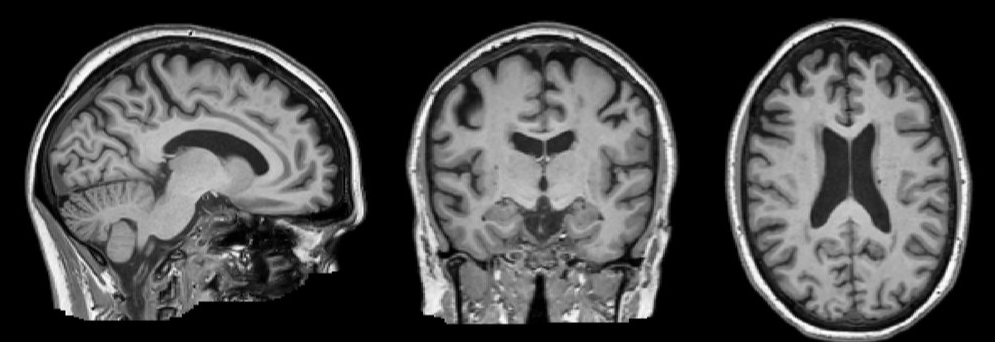

- 환자의 체위를 변화시키지 않고 횡단면(axial), 시상면(sagittal), 관상면(coronal)의 영상을 얻을 수 있음.

(may be taken in very many different planes without having to move the patient)

구조적 자기공명영상 (Structural magnetic resonance imaging)

: a non-invasive technique for examining the anatomy and pathology of the brain